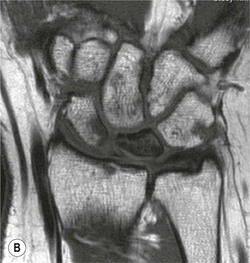

Spontaneous AVN of the lunate is known as Keinböck's disease. The radiographic and MRI features are the same as AVN of the scaphoid (Fig. 46-26). It may be associated with negative ulnar variance (short ulna). Advanced bony collapse in both proximal scaphoid fractures and AVN of the lunate results in late-stage secondary osteroarthritis.

Tears of the ligaments of the wrist can result in carpal instability. Disruption of the intrinsic ligaments results in intercalated segment instability. This is also termed dissociative carpal instability because there is dissociation between the segments of the proximal carpal row.

The scapholunate ligament is most frequently involved. Radiographs may show scapholunate diastasis (>3 mm). The lunate demonstrates dorsal rotation on lateral views and volar rotation of the scaphoid. This results in an increase in the scapholunate angle (>60°) known as dorsal intercalated segment instability (DISI) (Fig. 46-27). A DISI deformity of the carpus may also be associated with fractures of the scaphoid.

Disruption of the lunotriquetral ligament is less common. In this situation there is volar rotation of the lunate on lateral radiographs, with reduction of the scapholunate angle (<30°). On PA radiographs there may be an obvious step between the distal articular surface of the lunate and triquetrum. This is termed volar intercalated segment instability (VISI).

More subtle degrees of instability may be demonstrated by an instability series of radiographs acquired with radial and ulnar deviation and with a clenched fist view. Video fluoroscopy is also useful for assessing dynamic wrist instability.

Abnormal communication between the radiocarpal and midcarpal joints may be seen on arthrography (Fig. 46-28), which is usually combined with MRI or CT16 (Figs. 46-29 and 46-30). However, direct visualisation of the ligaments is possible with conventional MRI. The most important features to describe that help determine management include the following: